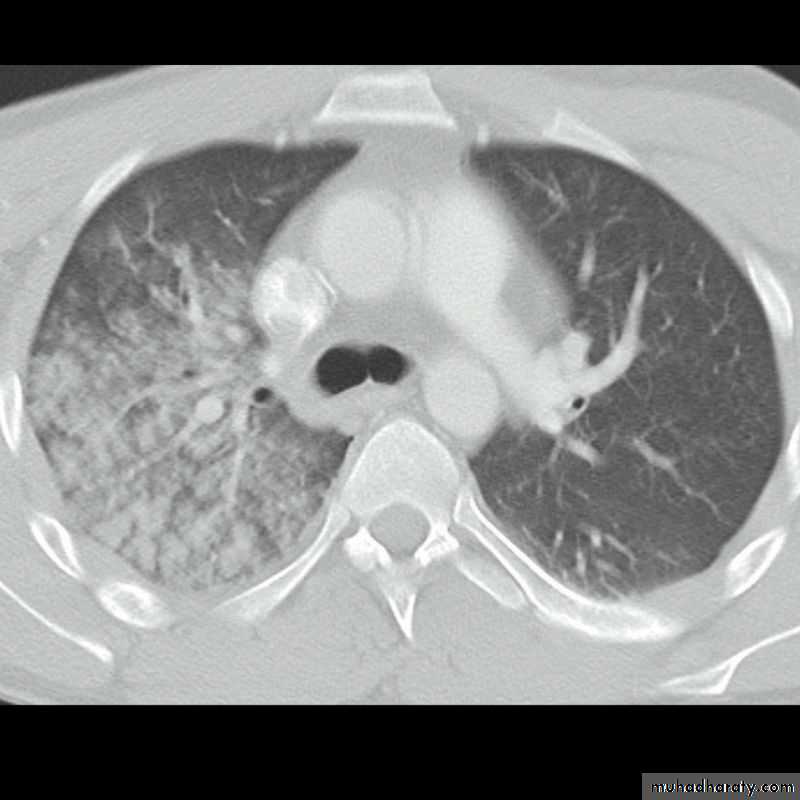

Patient with fever, rigor and dyspnea